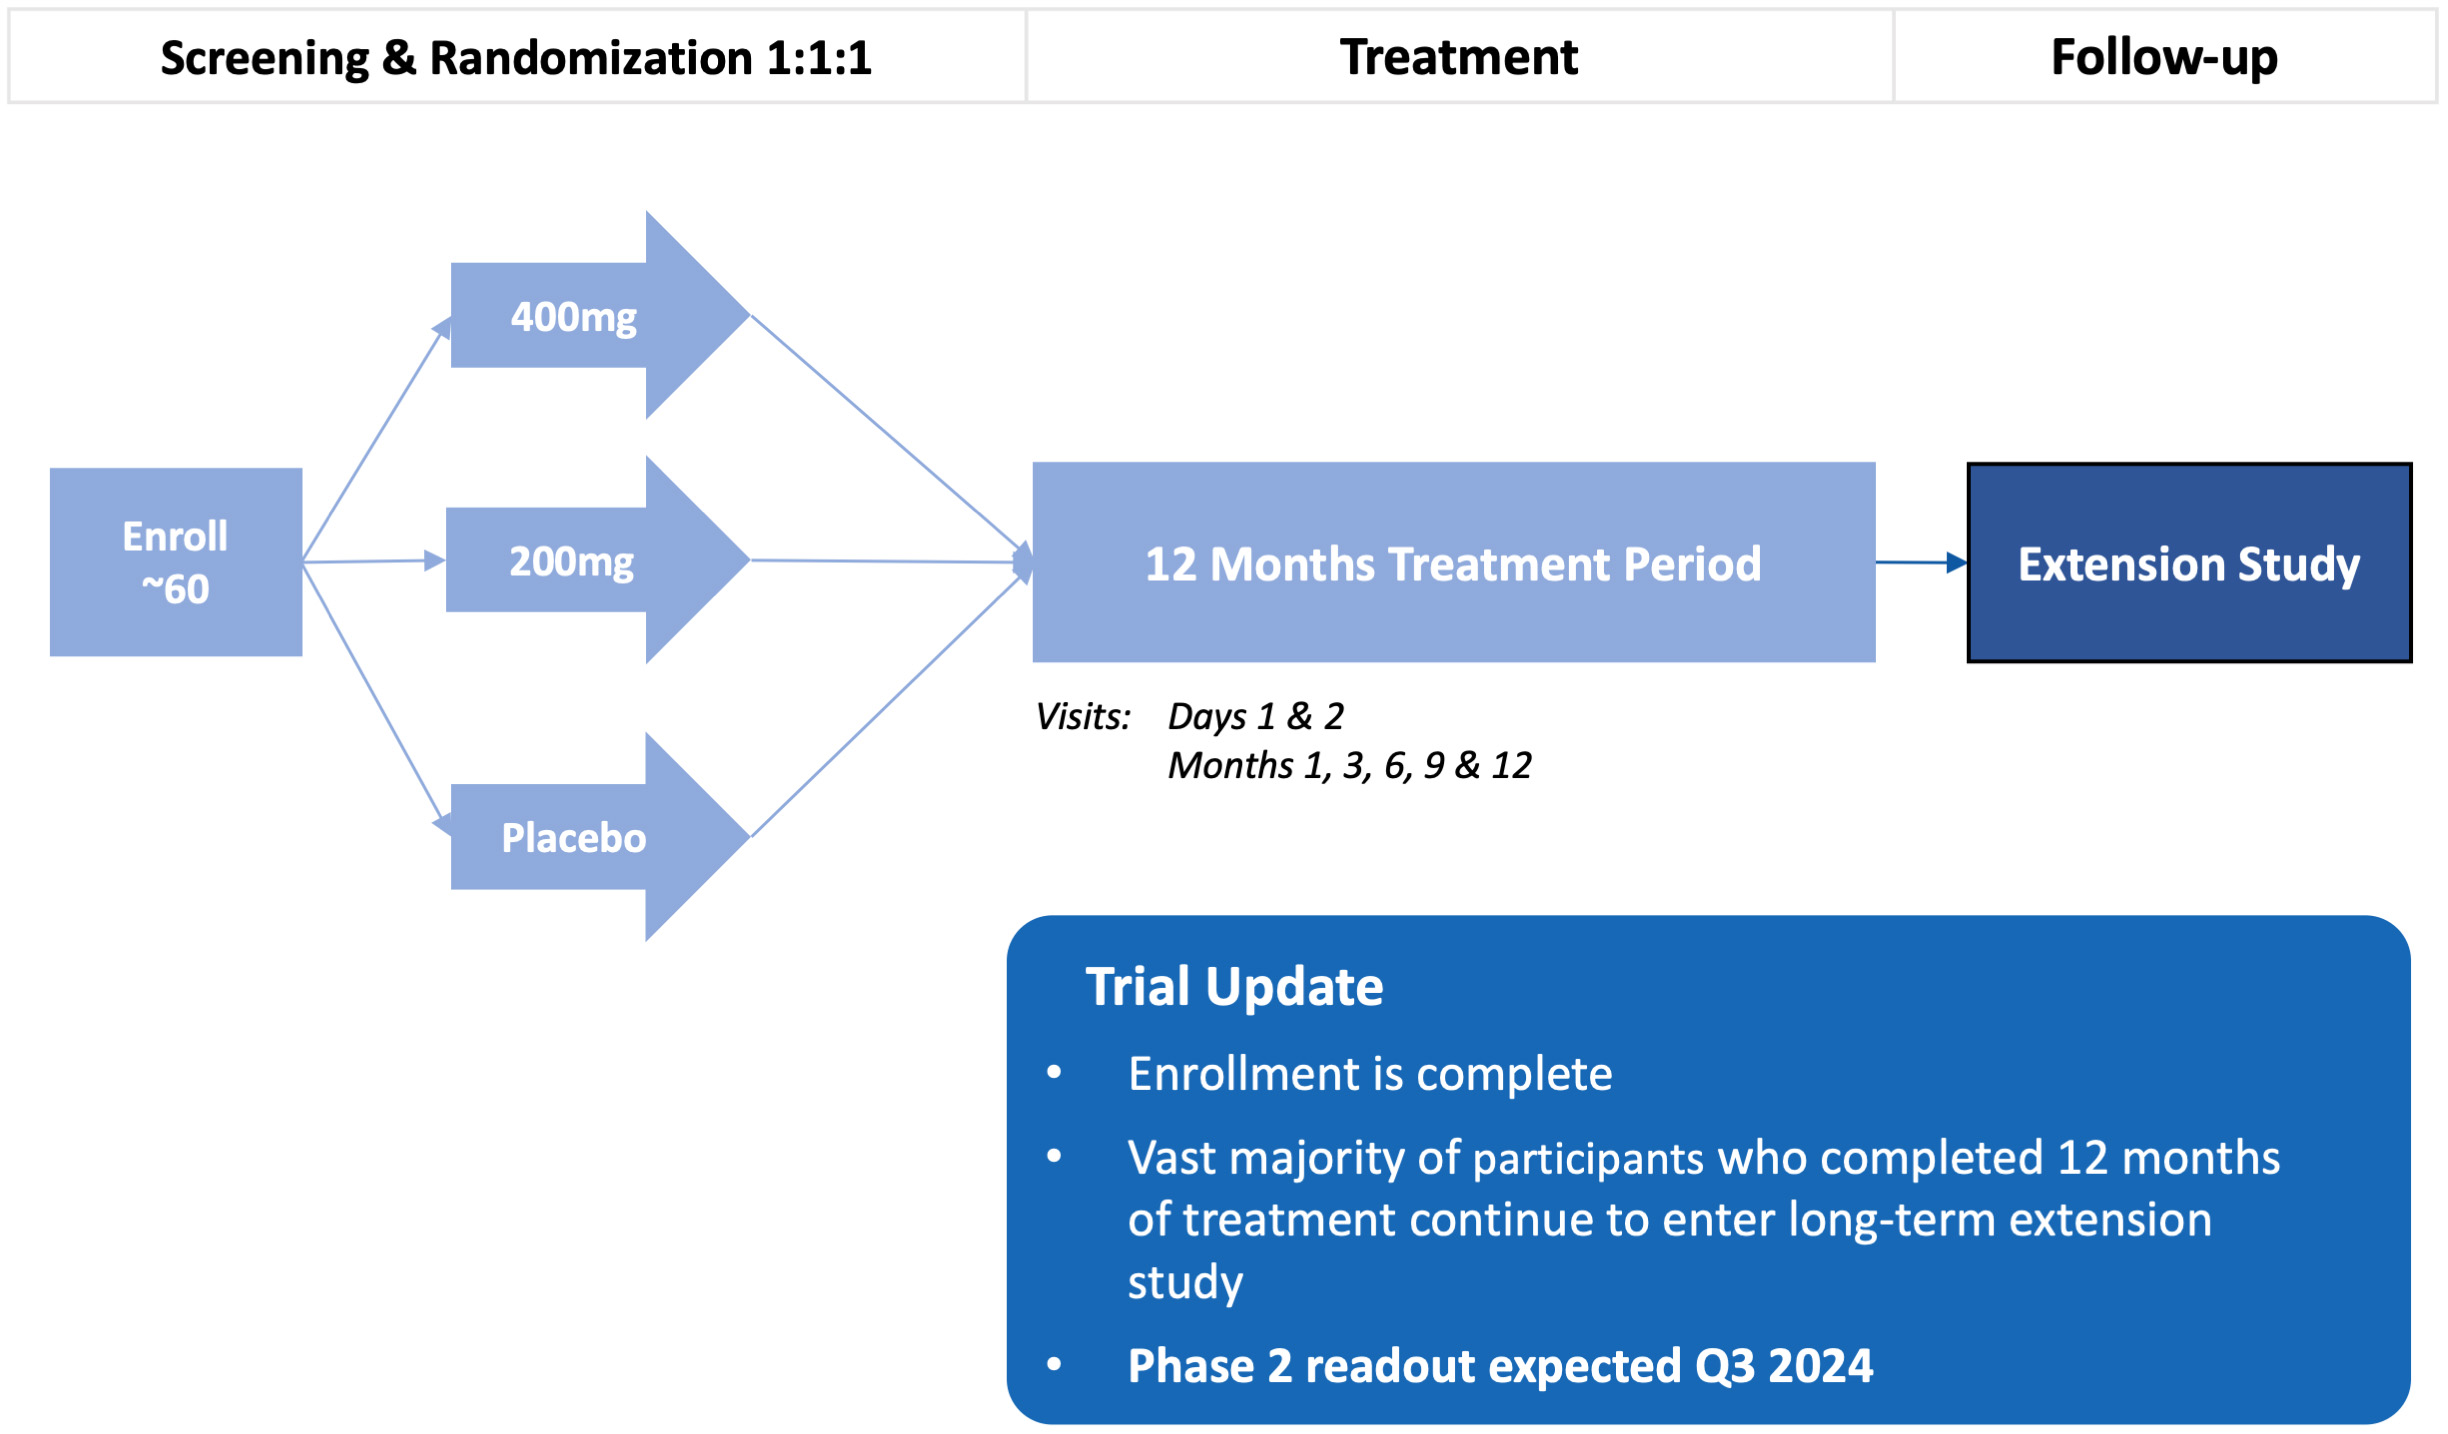

•Five phase 2 clinical-stage programs with multiple upcoming data readouts expected, including REC-994 in cerebral cavernous malformation (CCM) in Q3 2024, REC-2282 in neurofibromatosis type 2 (NF2) in Q4 2024, REC-4881 in familial adenomatous polyposis (FAP) in H1 2025, and REC-4881 in AXIN1 or APC mutant solid tumors in H1 2025